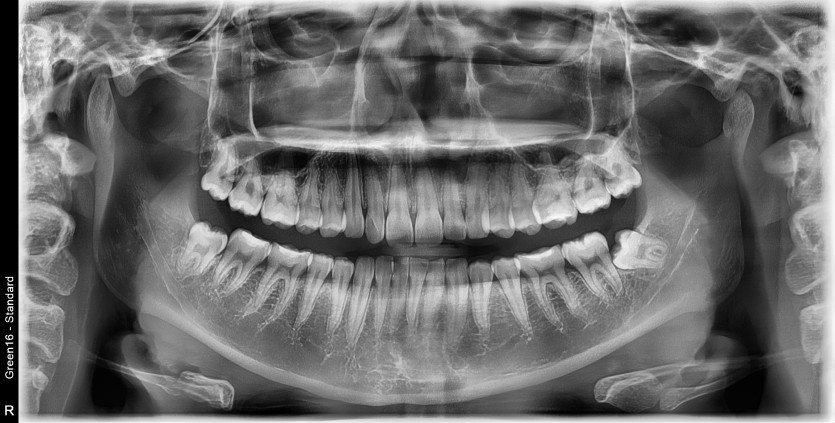

#38,48 사랑니 발치

구강 외과 전문의가 당일 발치했습니다.